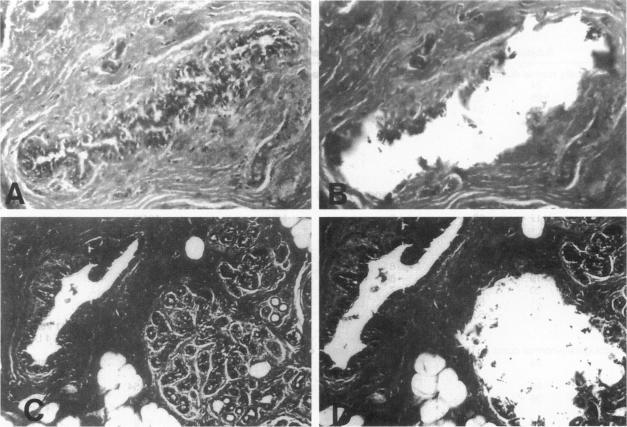

组织学正常的乳腺组织中的基因异常克隆。

Genetically abnormal clones in histologically normal breast tissue.

Breast cancer is believed to develop as multiple genetic abnormalities accumulate, each conferring some growth advantage, but the timing and nature of the earliest steps in this progression are not yet elucidated. Proliferative breast lesions, associated with an increased risk of breast cancer although considered benign, recently were shown to contain clonal genetic abnormalities. Therefore, we hypothesized that clonal genetic abnormalities might be detectable before any phenotypic abnormalities are evident, ie, in histologically normal breast tissue. We examined DNA extracted from 95 normal-appearing breast ducts or terminal ductal-lobular units from 20 individuals at varying degrees of risk (those undergoing reduction mammoplasties, those with atypical hyperplastic proliferative lesions, and those already diagnosed with breast cancer). Using nine microsatellite markers, we sought evidence of genetic instability or of allelic imbalance (most likely representing loss of heterozygosity). We found genetically abnormal clones in 21/95 (22%) seemingly normal samples from 10/20 (50%) women from all three risk groups. In women under age 50, trends toward increased rates of abnormalities were noted with increased cancer risk. The abnormalities identified were more likely to be at sites of known or postulated tumor suppressor genes rather than at random or neutral loci. Our data indicate that genetic abnormalities potentially critical to breast tumorigenesis accumulate before pathological detection even of high-risk lesions and are detectable in tissue that is not only histologically benign but also completely normal.

乳腺癌被认为是随着多种基因异常的积累而发展的,每一种异常都赋予一定的生长优势,但这一进程中最早步骤的时间和性质尚未阐明。增殖性乳腺病变虽被认为是良性的,但与乳腺癌风险增加相关,最近研究表明其含有克隆性基因异常。因此,我们推测在任何表型异常出现之前,即组织学正常的乳腺组织中,可能检测到克隆性基因异常。我们检测了来自20名处于不同风险程度个体(接受乳房缩小整形术者、有非典型增生性增殖性病变者以及已被诊断为乳腺癌者)的95个外观正常的乳腺导管或终末导管小叶单位提取的DNA。使用9个微卫星标记,我们寻找基因不稳定或等位基因失衡的证据(最可能代表杂合性缺失)。我们在来自所有三个风险组的10/20(50%)女性的21/95(22%)看似正常的样本中发现了基因异常克隆。在50岁以下女性中,随着癌症风险增加,异常率有上升趋势。所识别的异常更可能出现在已知或推测的肿瘤抑制基因位点,而非随机或中性位点。我们的数据表明,对乳腺肿瘤发生可能至关重要的基因异常在病理检测出高危病变之前就已积累,并且在不仅组织学上为良性而且完全正常的组织中也可检测到。